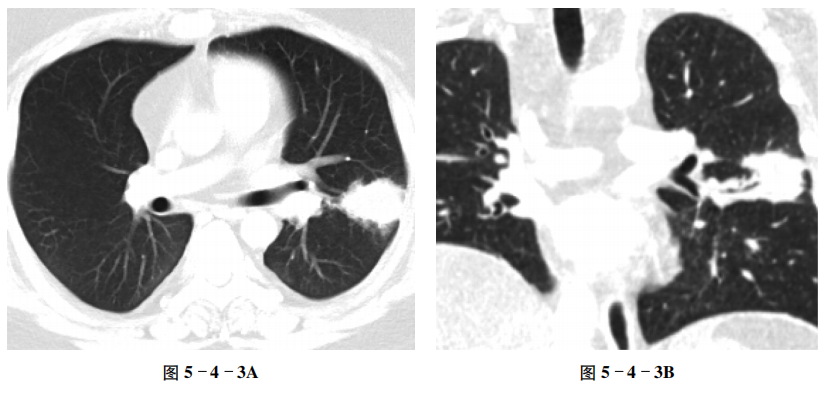

例3 球形肺炎

【病史摘要】 男性,27岁。因咳嗽、咳痰1个月,痰中带血半月入院,痰查癌细胞阴性。

【CT征象】 左肺下叶背段可见一球形密度增高影,边界欠清,可见少许短粗条索影;重组冠状位图像可见其肺门侧支气管通畅;纵隔窗病灶呈软组织密度;增强扫描病变呈不均匀较明显强化(图5-4-3A~C)。

【重要征象】 球形密度增高影,边界欠清,病灶内侧支气管通畅;增强扫描呈较明显强化。

【CT拟诊】 ① 球形肺炎。② 周围型肺癌。③ 肺结核瘤。

【最终诊断】 球形肺炎。